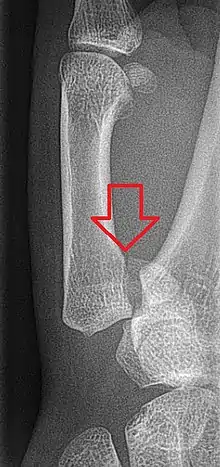

Fratura de Bennett

Fratura de Bennett é uma ruptura da base do polegar, mais especificamente da primeira articulação carpo-metacarpal, formada pela epífise proximal do primeiro metacarpo e pelo osso trapézio. É o tipo mais comum de fratura do polegar, pode ser causado por queda sobre mão aberta ou ao golpear contra um objeto duro. Essa fratura intra-articular é quase sempre acompanhada por algum grau de deslocamento dos ossos (luxação) da articulação carpometacarpiana (CMC).[1]

Se há 3 signos clínicos de fratura deve-se pedir uma radiografia de mão, frente e perfil.